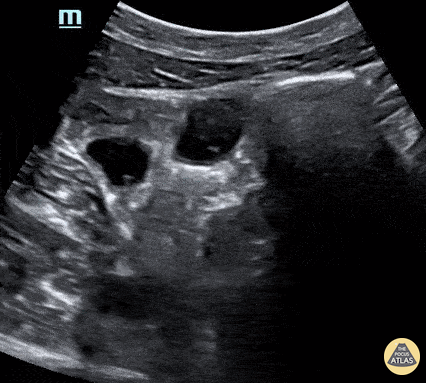

51 year old male presented with a chief complaint of abdominal pain for 3 days with nausea and vomiting. The curvilinear probe was used to evaluate the aorta with an incidental finding (shown) of clear peristalsis of the bowel contents with hypoechoic and anechoic contents. In this segment it is clear there is no obstruction. Lindsay Davis, DO, MPH, @Lindsadavis18 Lydia Mansour, DO Emily Nagourney, MS4 Central Michigan University